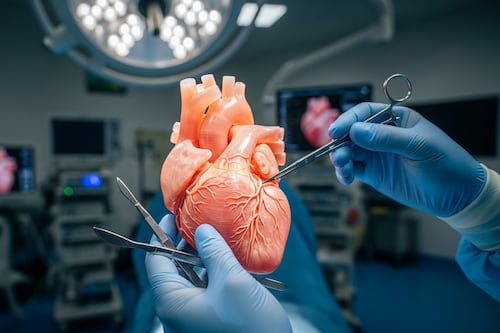

Así es el corazón impreso en 3D que permite a los cirujanos “ensayar” el éxito antes del primer corte

Un corazón artificial impreso en 3D con textura real permite ensayar cirugías cardíacas.